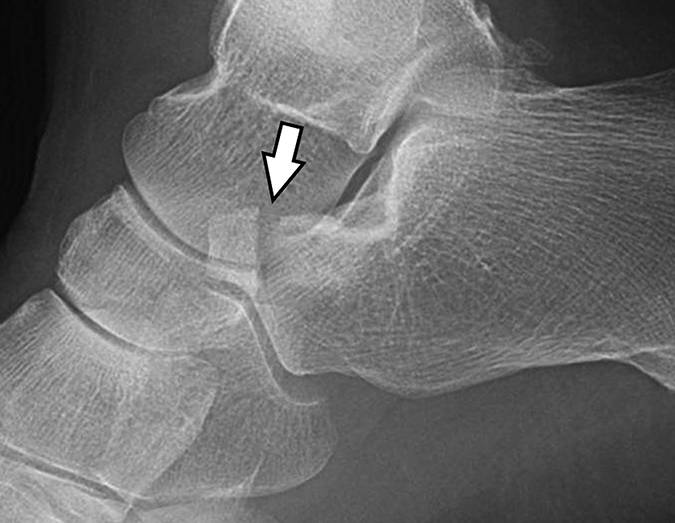

图7A-25岁的男子在滑雪时跌倒。侧位片显示跟骨骨折应于2型骨折(箭头)。

图 7B - 脚的斜位片识别骨折(箭头)。